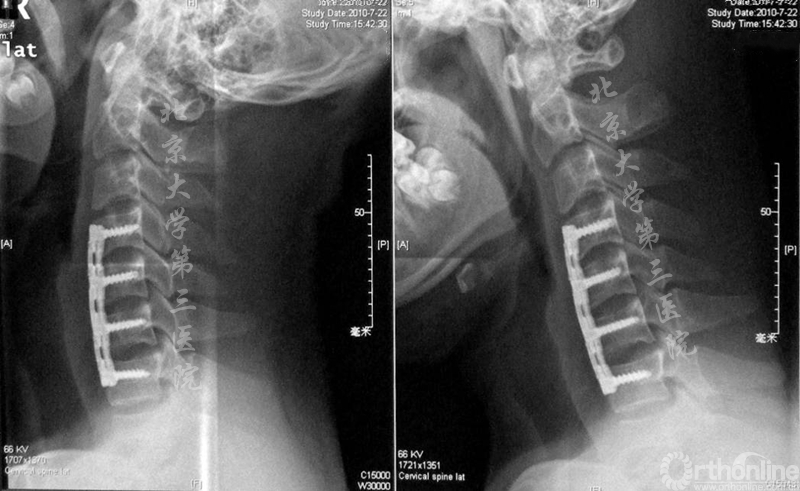

术前屈伸位X线

术后1年屈伸位X线